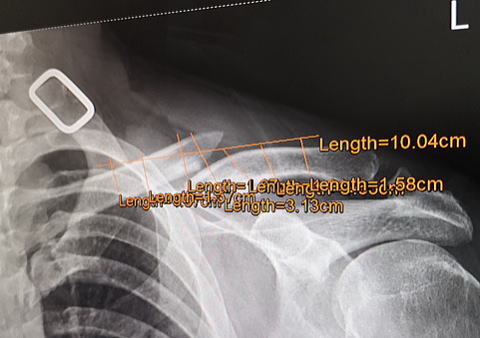

つづいてXレイに移動して肺の検査でレントゲン=OK、

1.jpg)

右(写真では左)の鎖骨は完治、左(写真では右)の鎖骨は

尖って折れて( ゚Д゚)ます。

「オレンジの書き込みのようにプレート入れてボルトで固定、

そして手術は基本的に1回のみ、痛みが無ければプレートは

そのまま、2回も手術したくないでしょ、手術は2時間、入院

は3日ほど、手術前3時間から飲食禁止です」 と。